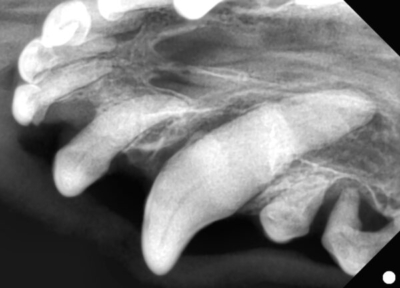

まず、全身麻酔をかけて歯科レントゲンを全ての歯で撮影します。

上顎切歯

上顎の切歯のレントゲン

黄色斜線部分が歯の周りの骨が溶けてしまったところ。

このようにひとつひとつの歯を評価していきます。